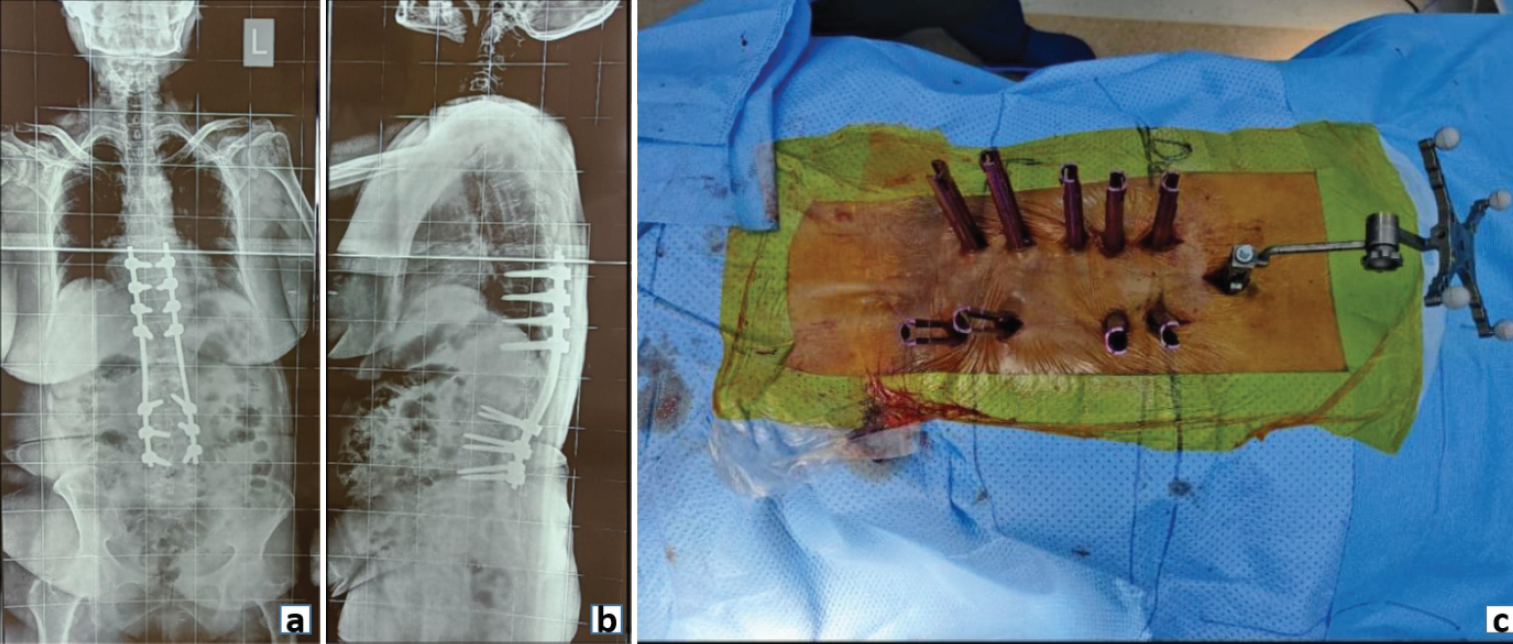

Few examples of spinal fixation include minimally invasive surgery (MIS) fixation in osteoporotic fracture spine, where the aim is to provide a long construct to maintain the alignment of the spinal column (Fig. 2).

Figure 2: Post-operative radiograph (a) Anteroposterior and (b) Lateral view showing posterior pedicle screw fixation in an osteoporotic fracture spine. (c) Clinical image demonstrating minimally invasive screw fixation in an osteoporotic spine.